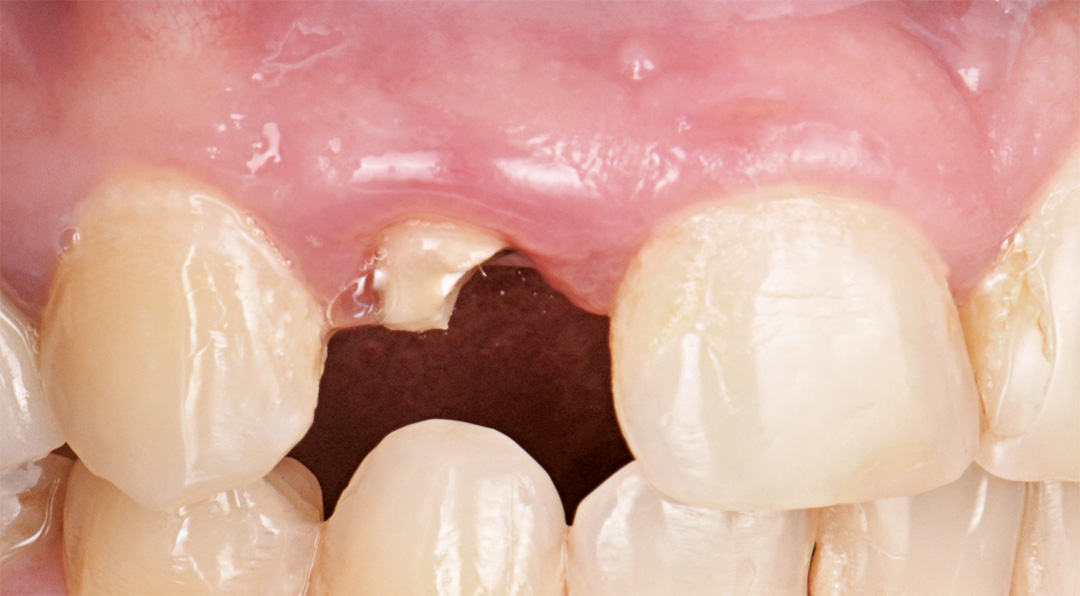

A patient presented with a horizontal fracture of the upper left lateral incisor (tooth 1.2), with no clinical signs of suppuration or bleeding. The periodontal phenotype was thin, and the buccal bone wall was minimally thick, increasing the risk of soft tissue recession following extraction. A minimally invasive and digitally planned treatment was chosen to preserve tissue architecture and ensure a predictable aesthetic result.

Surgery and initial outcomes